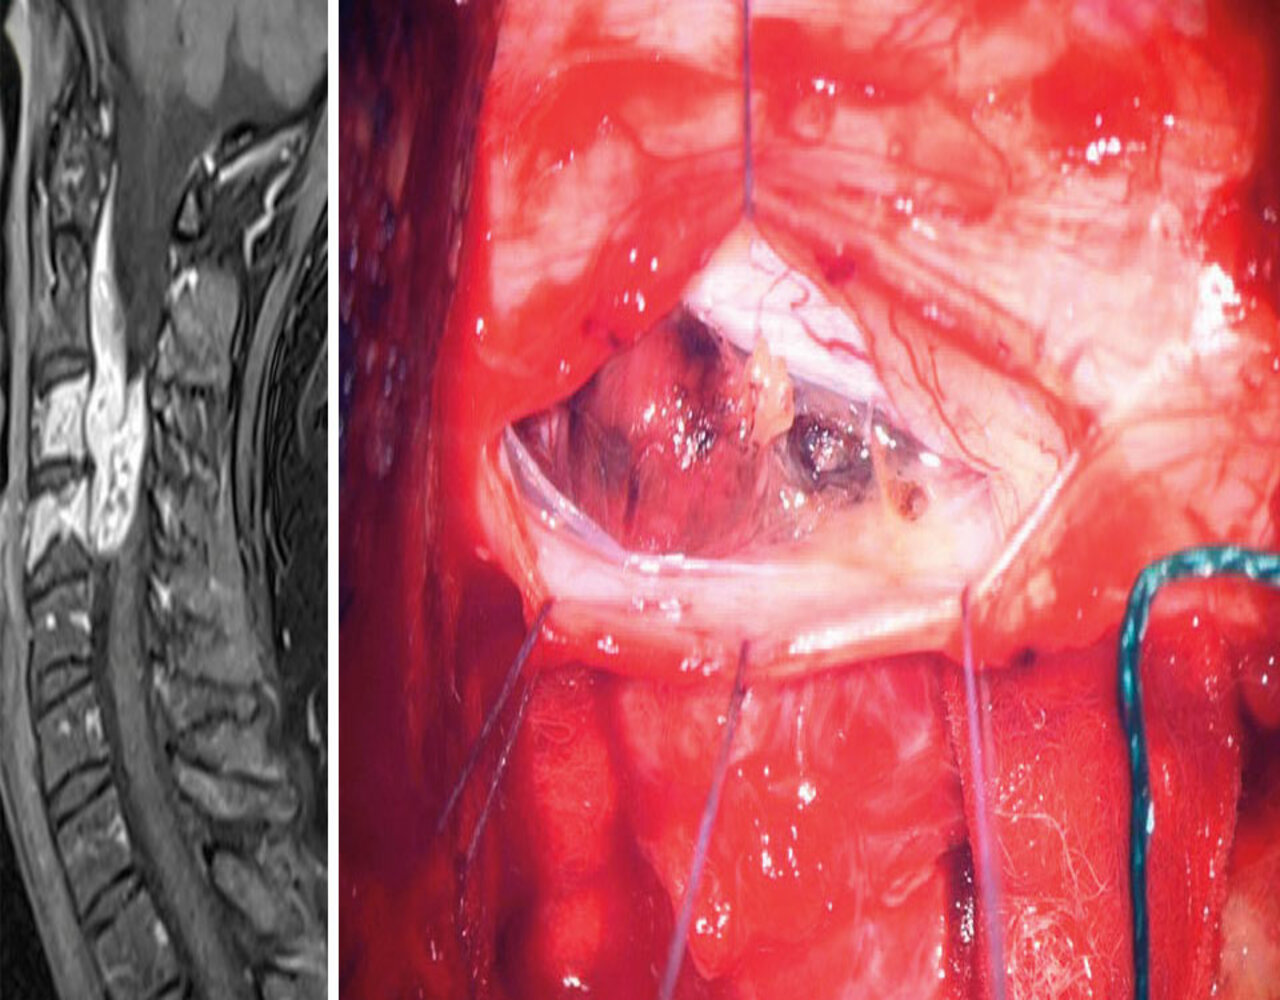

Fall 3

Eine 53-jährige Patientin litt seit mehr als drei Jahren an linksseitigen Nacken- und Armschmerzen und intermittierenden Dysästhesien. Zusätzlich entwickelte sie eine progrediente Gangstörung. Als Ursache fand man ein großes, teils zystisch wachsendes Schwannom im Bereich der mittleren HWS mit intra- und extraspinaler Ausdehnung. Es hatte bereits die Halswirbelkörper 3 und 4 destruiert, die linke Vertebralarterie ummauert und war weit in den oberen Armplexus vorgedrungen.

Therapeutisch erfolgte zunächst eine Laminektomie mit Resektion der befallenen Vertebralgelenke. Zehn Tage später wurden HWK 3 und 4 durch ein Implantat ersetzt. Den weit in die Halsweichteile reichenden Tumor konnten die Chir­urgen nur subtotal entfernen. Postoperativ ist die Patientin asymptomatisch und der Resttumor zeigt auch neun Monate nach dem Eingriff keine Progredienz.